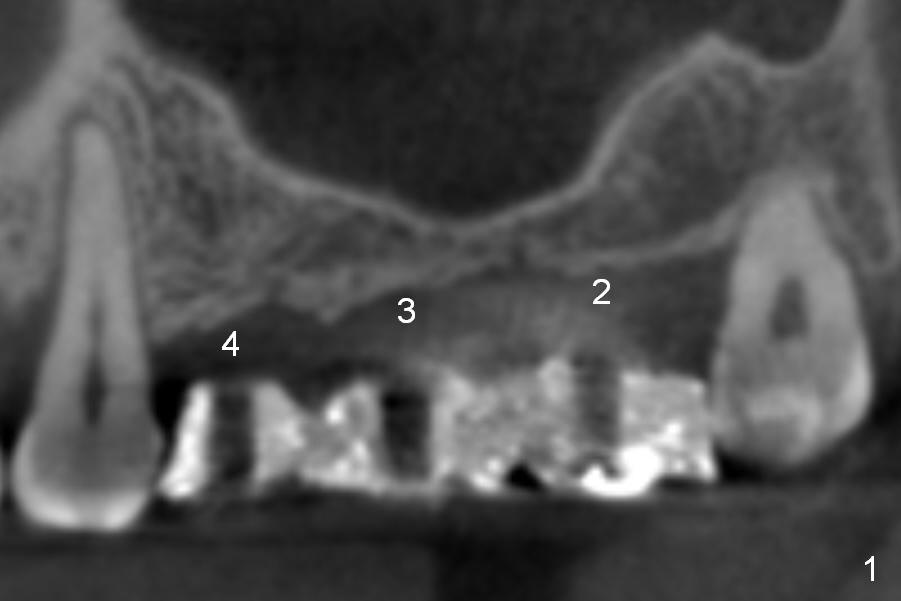

A 49-year-old lady has lost #2-4 for quite a while (Fig.1, no indication for antibiotic study (for cases with <6 months post extraction)). Bone height at #2 and 3 is limited. Use a 2 mm pilot drill to start osteotomy with rubber stopper at 4 mm, followed by insertion of 2 short parallel pins (PP) at #2 and 3 (Fig.2,4,6,8). The PPs may be not stable because of shortness. At #4 (8 mm initially), insert a marked PP for PA. If the position and trajectory of each osteotomy is correct, use trephine burs for further osteotomy at #2,3, since they have labels of 2,4,6 mm. For example small one at 4 mm, larger one at 6 mm. If the bone stays in place after trephine bur usage, use Bicon osteotomes to do sinus lift. Allograft and Osteogen is to be loaded in small syringes (x4). Previous implant surgeries indicate that the bone density of the maxilla is high (1,2). CT shows variable density (compare Fig.1 vs. 2, 3 vs. 4 et al). The density at the medulla is low; that at the cortices high. The patient plans to have 2 implants. If the implant at #3 is not stable, the implant at #2 will be needed for splinting.